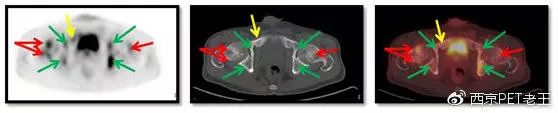

我们又把CT调整到骨窗,看骨骼病变的情况,可以看到全身绝大部分骨骼都有转移,但骨质结构破坏不明显(中列),说明这种是早期的骨转移,如下图:

红色箭头:股骨头转移;绿色:髋臼转移;黄色:耻骨转移